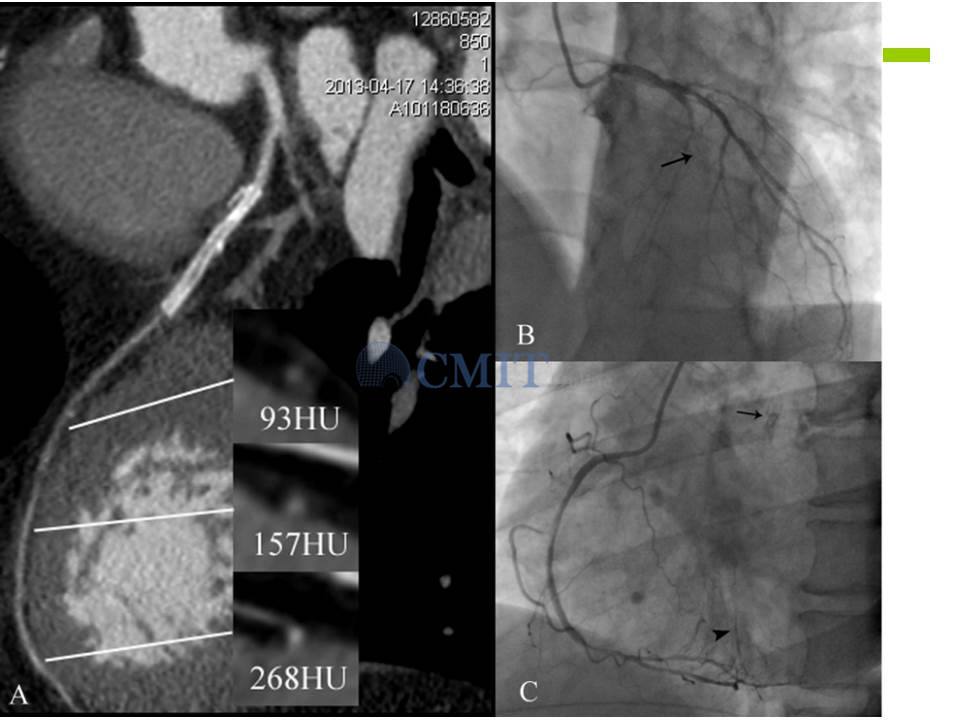

冠脉CTA读片技巧:如何判断支架内再狭窄?